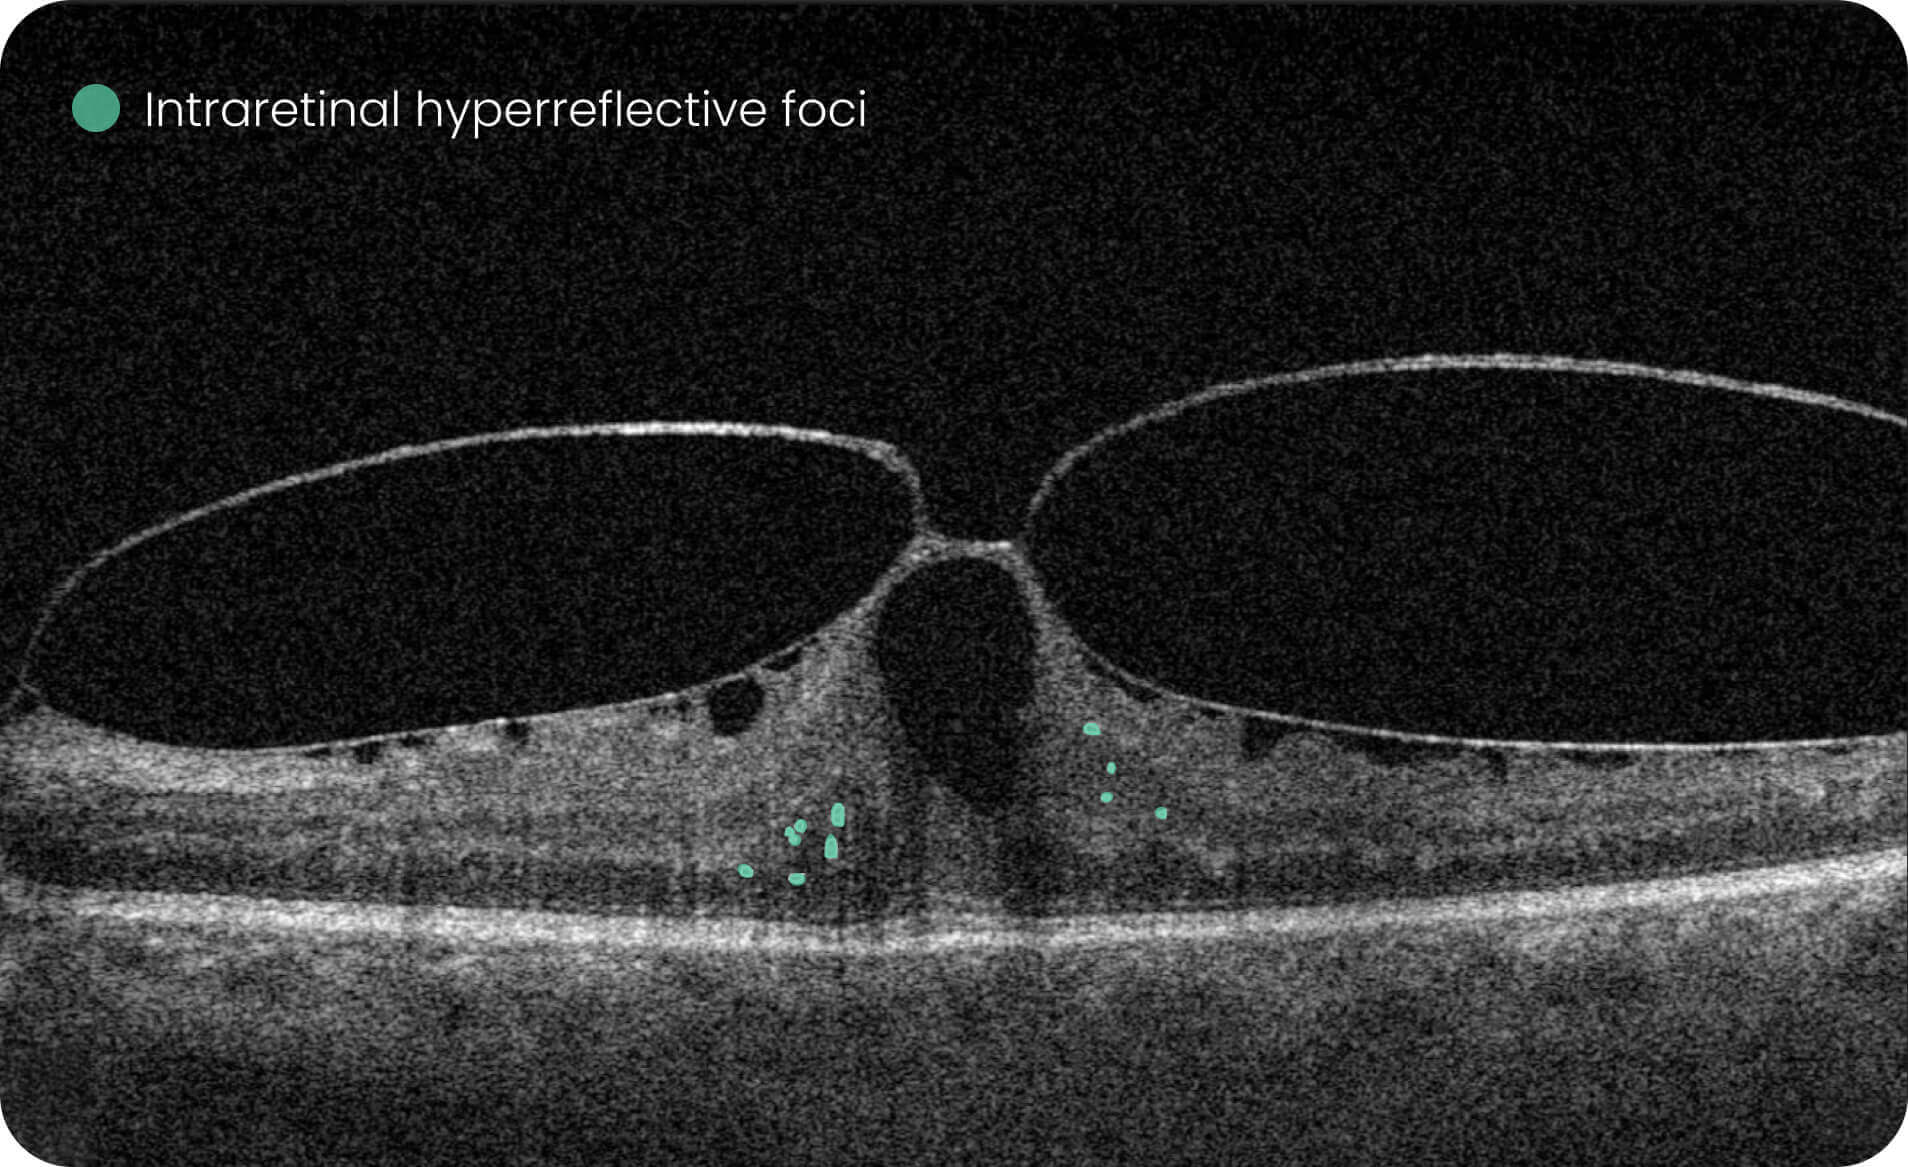

Characterization and visualization of OCT features commonly studied in Geographic Atrophy (GA), including hypertransmission, RPE atrophy, neurosensory retinal atrophy, and EZ changes.

Quantitative, image-derived measurements of GA-related features and associated biomarkers for research analyses.

- 40+retinal biomarkers studied in research across 30+ retinal conditions. For Research Use Only. Not for diagnostic procedures.

- Quantitative exploration of 40+ biomarkers for Research Use Only. Not for diagnostic procedures.